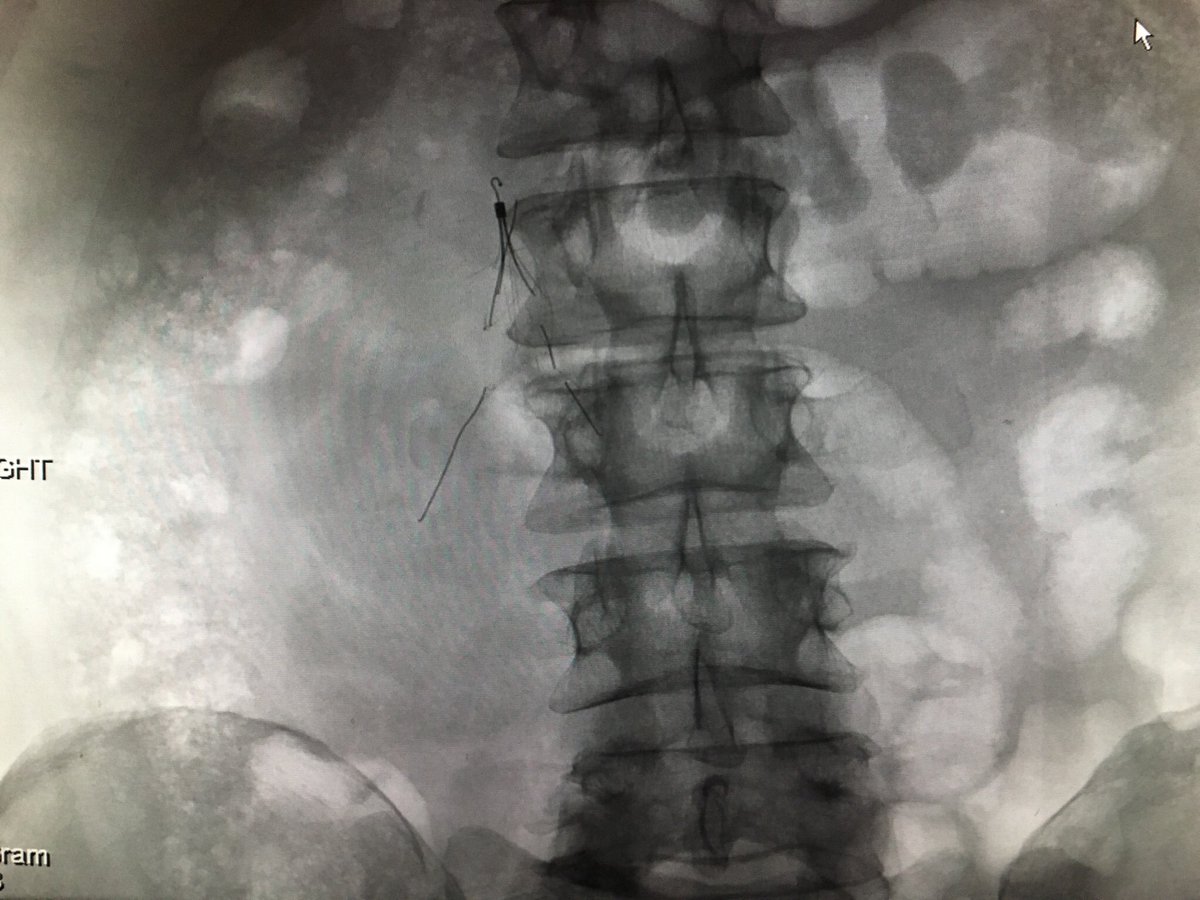

@kmadass

Filter Out Friday fun w/ @arslanmd @jtass6 @roshah31 5yr old embedded Venatech!! #laserlife #GTFO @rkryu @kush_r_desai @IvcFilterClinic